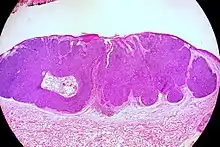

Fibroepithelioma of Pinkus | Anastomosing epithelial strands in a fenestrated pattern[32] | Most commonly occurs on the lower back.[28]: 748 [29]: 648 | ![]() |